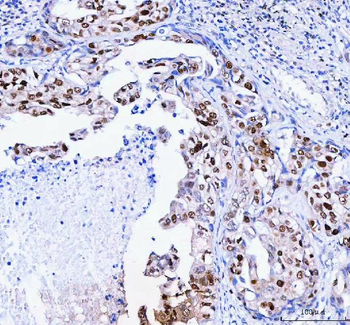

![Anti-FEN1 [SAIC-21C-4]](/images//pub/media/catalog/product/NewWebsite/35/orb1089994_1.png)

![Anti-FEN1 [SAIC-21C-4]](/images/pub/media/catalog/product/NewWebsite/35/orb1089994_2.png)

![Anti-FEN1 [SAIC-21C-4]](/images/pub/media/catalog/product/NewWebsite/35/orb1089994_3.png)